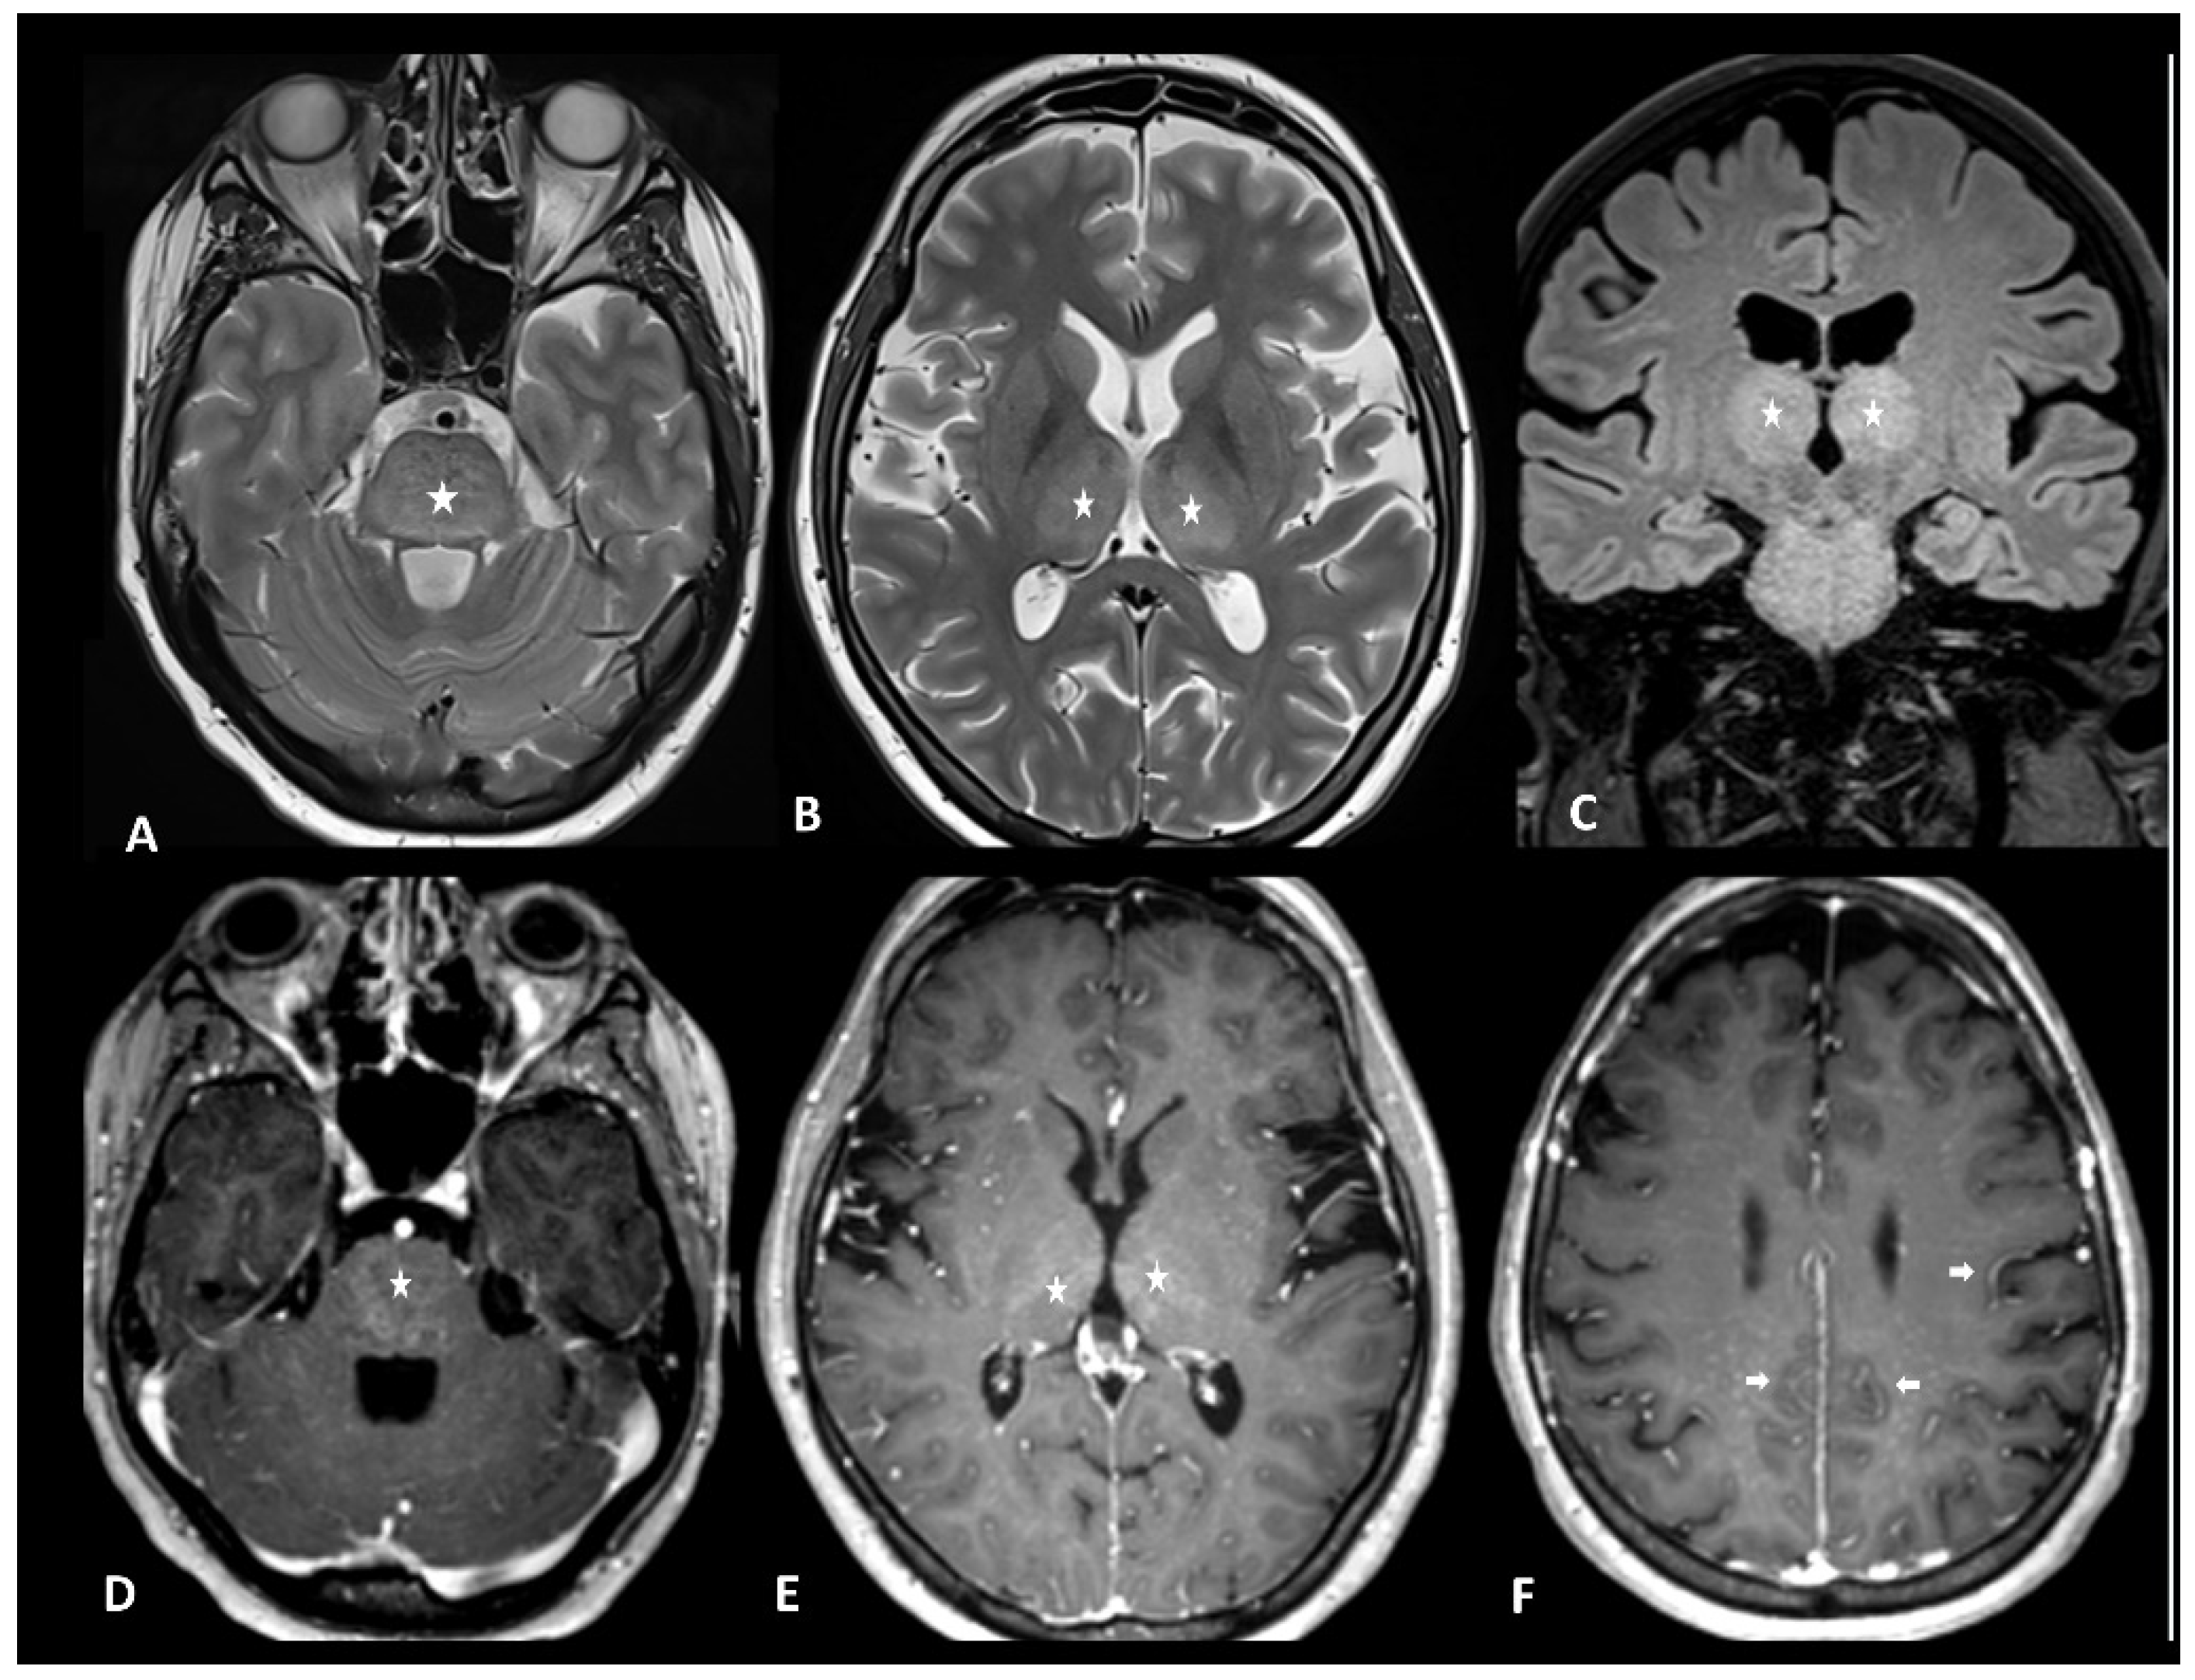

2.1.1. Ir-Encephalitis

| CNS | Encephalitis | CE brain MRI + LP + EEG + autoantibodies | Infectious encephalitis, disease progression | Mesiotemporal T2/FLAIR hyperintensities |

| Demyelinating disease | CE brain and spine MRI + LP + antibodies +/− CE optic nerve MRI | Multiple sclerosis, neuromyelitis optica spectrum disorder, transverse myelitis, isolated optic neuritis | Cortical, juxtacortical, periventricular, or infratentorial T2/FLAIR hyperintensities +/− enhancement | |

| Transverse myelitis | CE spine MRI + LP + autoantibodies | multiple sclerosis, neuromyelitis optica spectrum disorder, infectious myelitis | T2 hyperintensities > vertebrae, patchy contrast enhancement | |